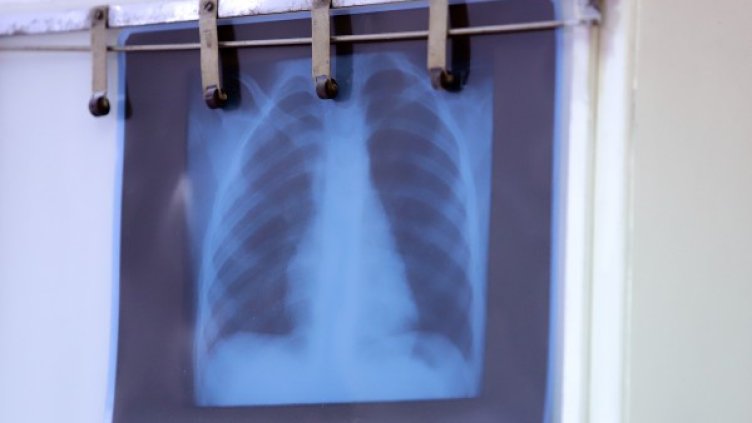

Увеличават се пациентите с пневмонии, заради усложнения от грип тип "Б" в Белодробната болница във Велико Търново, съобщи д-р Стела Денчева, управител на Специализираната болница за активно лечение на пневмо-фтизиатрични заболявания "Д-р Трейман".

Тя уточни, че само за вчерашния ден са приети 10 пациента с подобни симптоми, които са насочени към лечебното заведение от спешните отделения в областта и от личните си лекари.

Капацитетът на отделението, в което се приемат хора със симптоми на грип и пневмонии е 54 легла, от които 7 са допълнително разкрити, в момента са заети 53 легла, но минималният срок, в който трябва да се лекуват хората с пневмонии е седем дни, което означава, че е възможно капацитетът да не достигне, отбеляза д-р Денчева пред БТА.